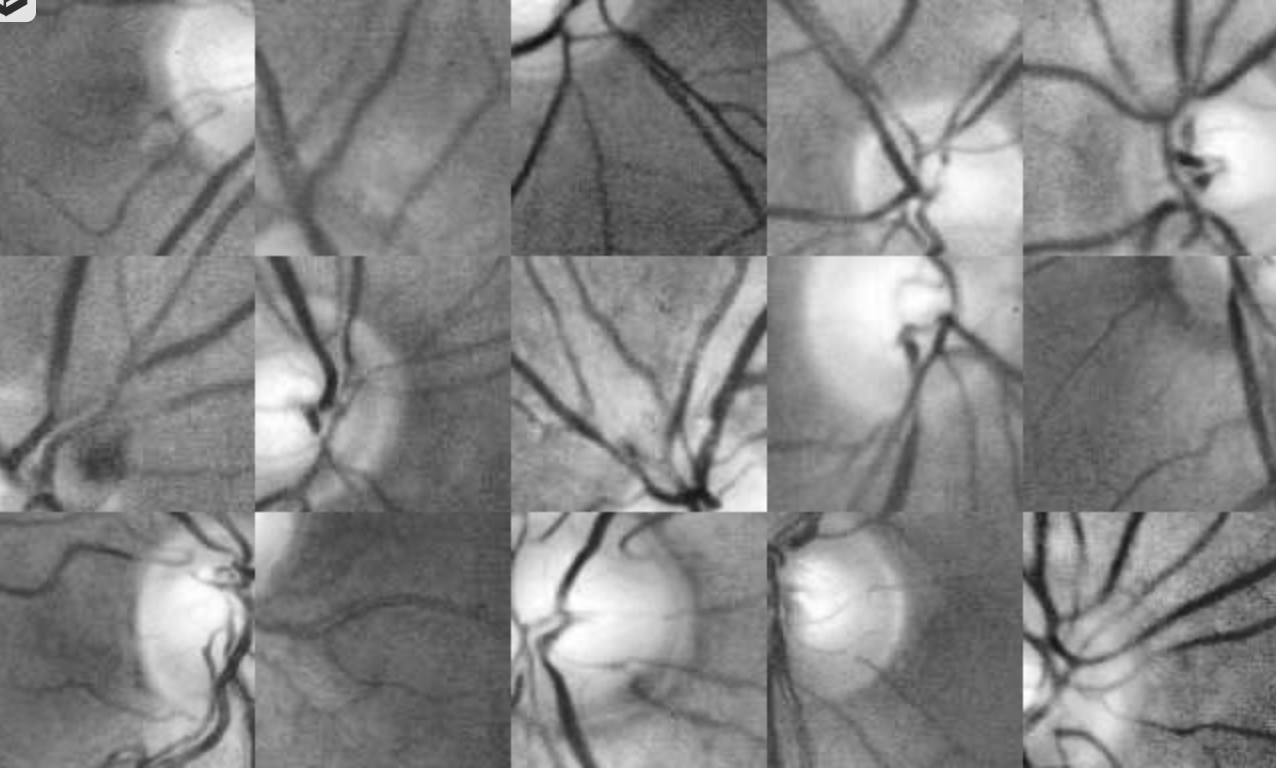

讯享网I use a modified Attention Unet which input of model is 128x128pix image patches. When sampling the patches, I focus the algorithm get samples around optic disc. The patches is like that: